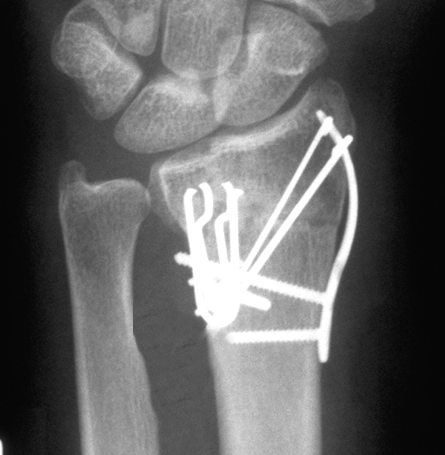

Case 1 Postop

Case 2 Postop

Case3 Postop

Case 4 Postop

Case 5 Postop

Case 6 Postop

Case 7 Postop

Case 8 Postop